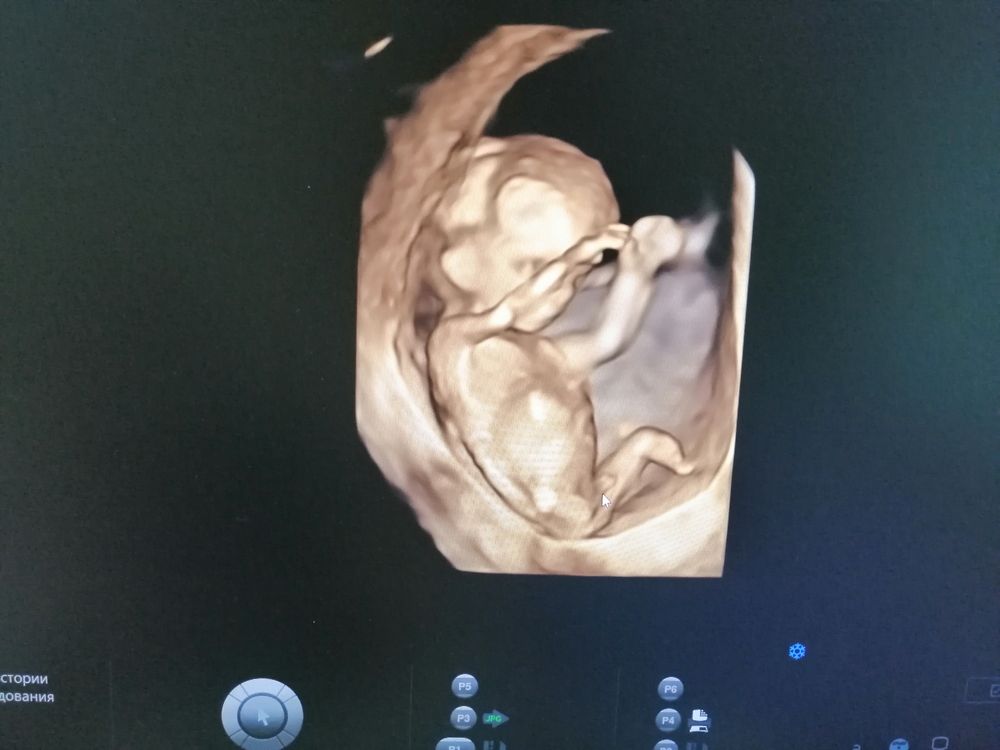

Помогите пожалуйста определить пол ребёнка. Мамочки нет сил ждать второй скрининг, может есть знающи

Если у Вас 12-я неделя, как тут показывает ББ, то пока ещё там половой бугорок, который и у мальчиков, и у девочек, по сути, одинаково выглядит. Там разница только в его наклоне относительно позвоночника. Но, глядя на ваши фото, сразу почему-то подумалось, что парень😊 Хотя первое вызывает вопросы: больше вижу девочку, но на этом сроке так не смотрят, поэтому может всё измениться чуть позже.

Юлия Sonnце, узист предположила, что мальчик, но для точного результата предложила ждать до 16 недели или второго скрининга. Да срок 12н2д.Просто так девочку хотелось

Не понятно, это может быть как мальчик так и отёкшие органы девочки . Вряд ли точно можно сказать, не зря даже врачи только после 16 недель могут определить

Вообще на таком сроке должен быть только половой бугорок,но у вас так торчит,что явно мальчик здесь,это ж точно не пуповина.